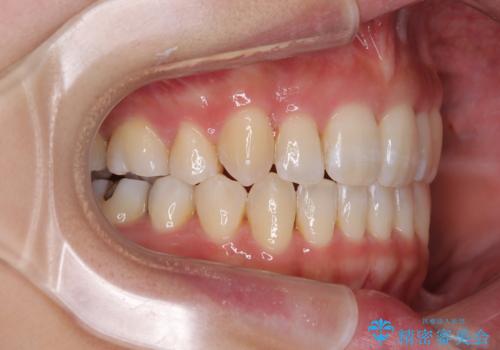

- 20代女性

- 目立つ八重歯を気にして来院された患者様です。

下顎歯列の叢生は軽度であることと、口元の突出感が全くなかったことから、八重歯解消のために上顎左右第一小臼歯を抜歯し、ワイヤー装置にて矯正治療を行うこととしました。